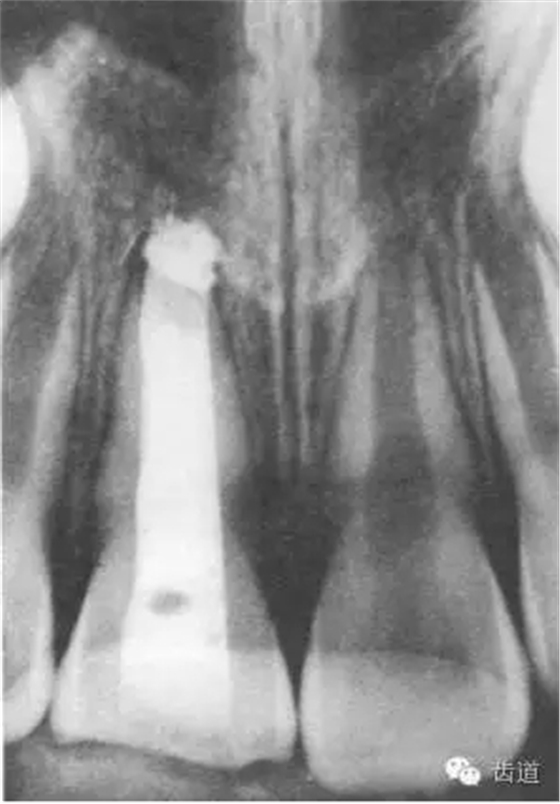

1.拍攝術(shù)前X線片;

3個(gè)月左右在X線片上可觀察到修復(fù)性牙本質(zhì)層的出現(xiàn), 術(shù)后6個(gè)月左右,常可觀察到連續(xù)的有一定厚度的修復(fù)性牙本質(zhì)層; 修復(fù)性牙本質(zhì)層的出現(xiàn),是間接牙髓治療成功的重要指征。

術(shù)后當(dāng)天

術(shù)后一個(gè)月

術(shù)后五個(gè)月

術(shù)后11個(gè)月